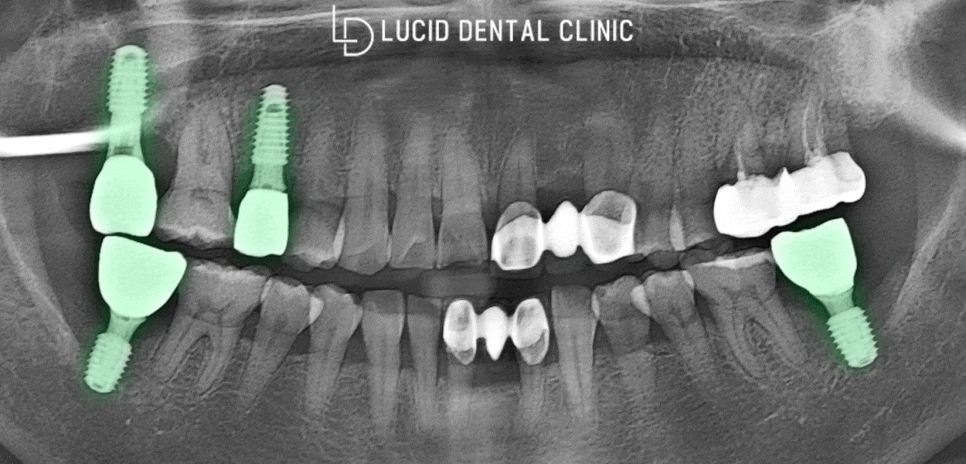

논현동 치과 에선 보다 빠르고

정교하게 픽스처를 식립하기 위해

디지털 가이드를 만들 예정입니다.

3D 구강 스캐너로 빠르게 분석하고,

디지털 모의 식립을 진행하게 되는데요

이를 통해 식립할 치조골 위치 및

깊이, 두께를 파악하게 됩니다 :)

또한, 모의 식립을 진행한 결과를 토대로

가이드를 제작하니 정교함이 두 배가 되죠.

논현동 치과 에서 시행한 가이드